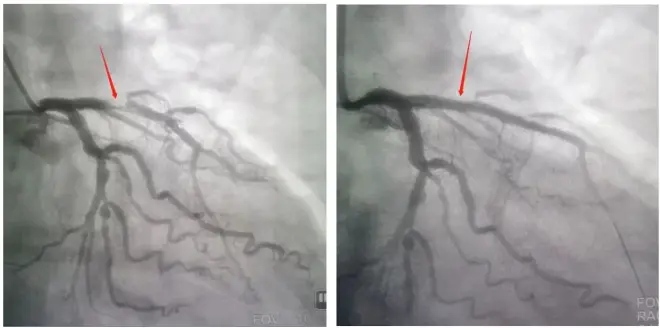

DSA是数字减影血管造影(Digital Subtraction Angiography)的英文缩写,其基本原理是将输入造影剂前后拍摄的两帧X线图像经数字化输入图像计算机,通过减影、增强和再成像过程把血管造影影像上的骨与软组织影像消除来获得清晰的纯血管影像。通俗的讲,就是将造影剂注入需要检查的血管即靶血管中,使血管结构显露原形,然后通过系统化处理,使血管显示更加清晰,便于进行医疗诊断或手术。

DSA主要用于观察血管病变,进行血管狭窄的定位测量,以及为介入治疗提供真实的立体图像,适用于心脑血管、外周血管及肿瘤等的检查和介入微创治疗。应用DSA技术进行介入治疗,为冠心病、心律失常、瓣膜病和先天性心脏病等心血管疾病的诊断和治疗开辟了一个新的领域。

2.DSA是显示冠状动脉的金标准。

相比CTA和MRA的无创检查,DSA是有创的血管造影,创伤微小,是业界公认的“金标准”,一般由临床科室的医师完成。检查时医生会在患者肘部或大腿根部的动脉开一个小口,进行动脉穿刺,将导丝和导管引导到需要检查的部位,可以高清实时动态观察血管的情况,检查耗时较长,一般需要20分钟以上。如果病情需要,可以同时进行介入治疗,比如溶栓、取栓、球囊扩张、植入支架等。